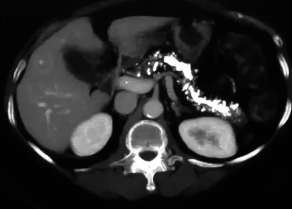

ct scan abdomen and acute panc

estimates severity and prognosis

complications → phlegmons, abscesses, pseudocysts. 2-3 wks after acute pancreatitis

pancreatic necrosis